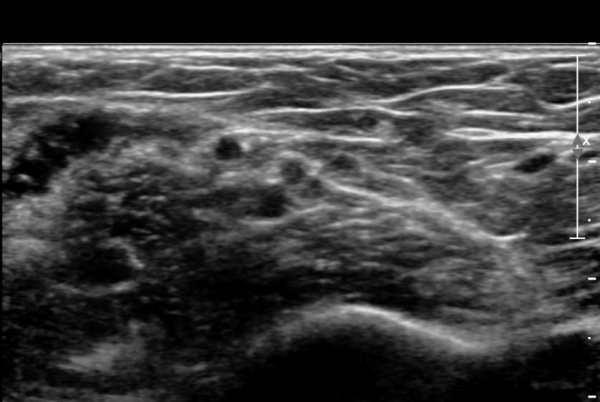

ŽÃËÀÚ¸¦ »ó¹ÚºÎ ¸»´ÜÀ¸·Î  ¿Å°Ü ÆÈ²ÞÄ¡ ºÎÅÍ ±ÙÀ§ºÎ·Î À̵¿ Çϸ鼭 Á¤Á߽Űæ Ⱦ´Ü¸é°Ë»ç¸¦

½ÃÇàÇÏ¿´´Ù(»çÁø 2).  ÆÈ²ÞÄ¡ ÁÖ¸§  ¾à  3cm ±ÙÀ§ºÎ¿¡¼­ Á¤Á߽ŰæÀÇ ÀϺΠ´Ù¹ß(fascicle)ÀÇ Àú¿¡ÄÚ ºÎÁ¾ÀÌ

°üÂûµÈ´Ù(»çÁø 3 , 4,  5,).

Á¤Á߽Űæ Á¾´Ü¸é °Ë»ç¿¡¼­µµ  Á¤Áß ½Å°æ ÀϺΠ´Ù¹ßÀÇ ¹æÃßÇü Àú¿¡Ä¿ ºÎÁ¾ÀÌ °üÂûµÈ´Ù(»çÁø 6, 7).